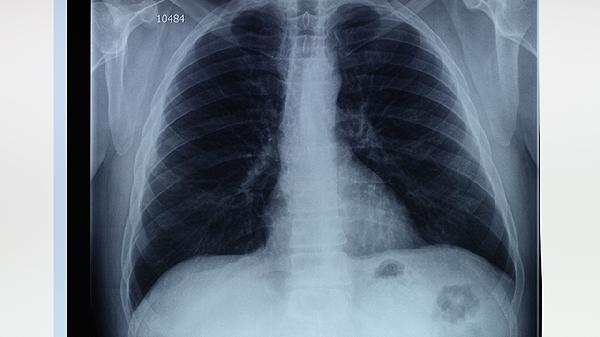

从病理检查来看,肺气肿患者肺泡间隔出现断裂和融合,肺大泡的壁由变薄的肺泡上皮组成,没有病毒包涵体或结核结节等传染性病变的特征。影像学上表现为透亮度增加的区域,这与感染引起的渗出影完全不同。